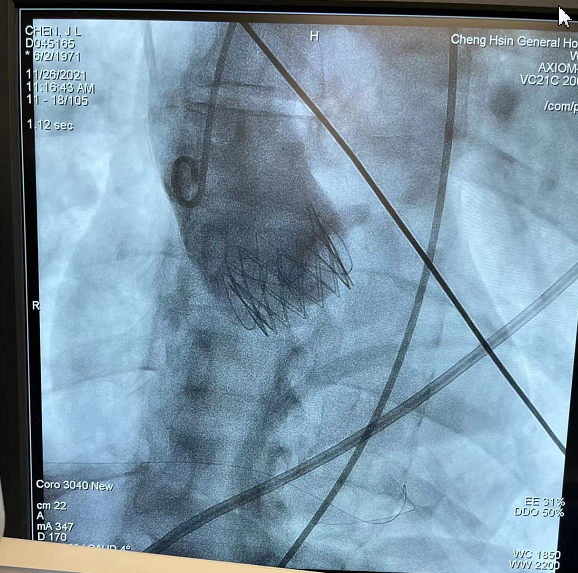

造影确认定位件入窦,瓣膜入座

瓣膜充分自膨